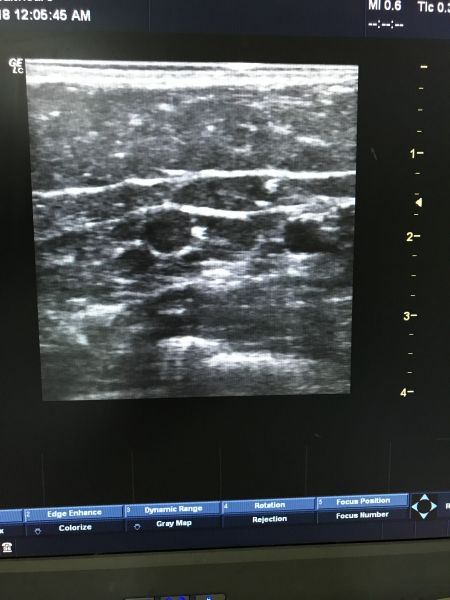

自2018年6月起,湘西州人民医院普三科成功开展超声引导下PICC置管技术,目前已完成200余例,无静脉血栓等并发症发生,为患者建立了安全的静脉通路,使患者的后续治疗得到保障。

“超声引导下PICC置管技术可减少药物外渗所致的静脉炎和皮肤破溃风险,利于药效充分发挥。”主任唐培志介绍道:对于肿瘤病患者来说,可提高化疗效果,适用于需要反复输入刺激性药物,且一次导管留置可使用一年。